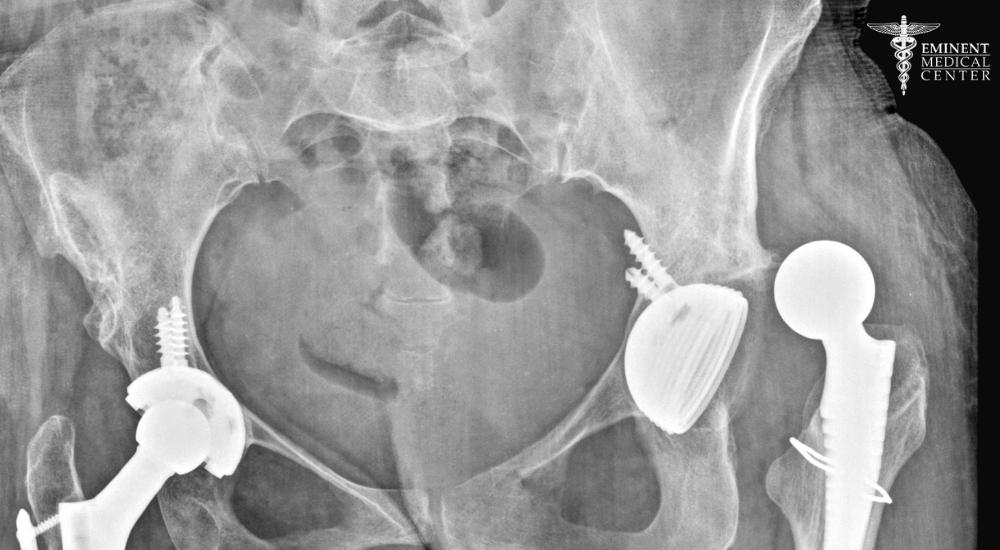

Hip Revision Surgery

Hip revision surgery is often necessary when a hip replacement fails due to loosening, infection, or a periprosthetic fracture. During this complex procedure, the surgeon removes the worn or damaged artificial hip components and replaces them with new parts designed to better support the hip joint.

Depending on the situation, complex surgical techniques may be necessary to address broken bones, scar tissue, or compromised blood vessels and nerves. Post-operative recovery typically involves physical therapy, blood clot prevention, and careful monitoring to prevent potential complications.

If your previous hip replacement is no longer working as it should, consider the benefits of a MAKO total hip replacement in Richardson and Dallas at Eminent Medical Center. This advanced technology allows for greater accuracy, better implant alignment, and a smoother recovery so you can get back to living without pain.